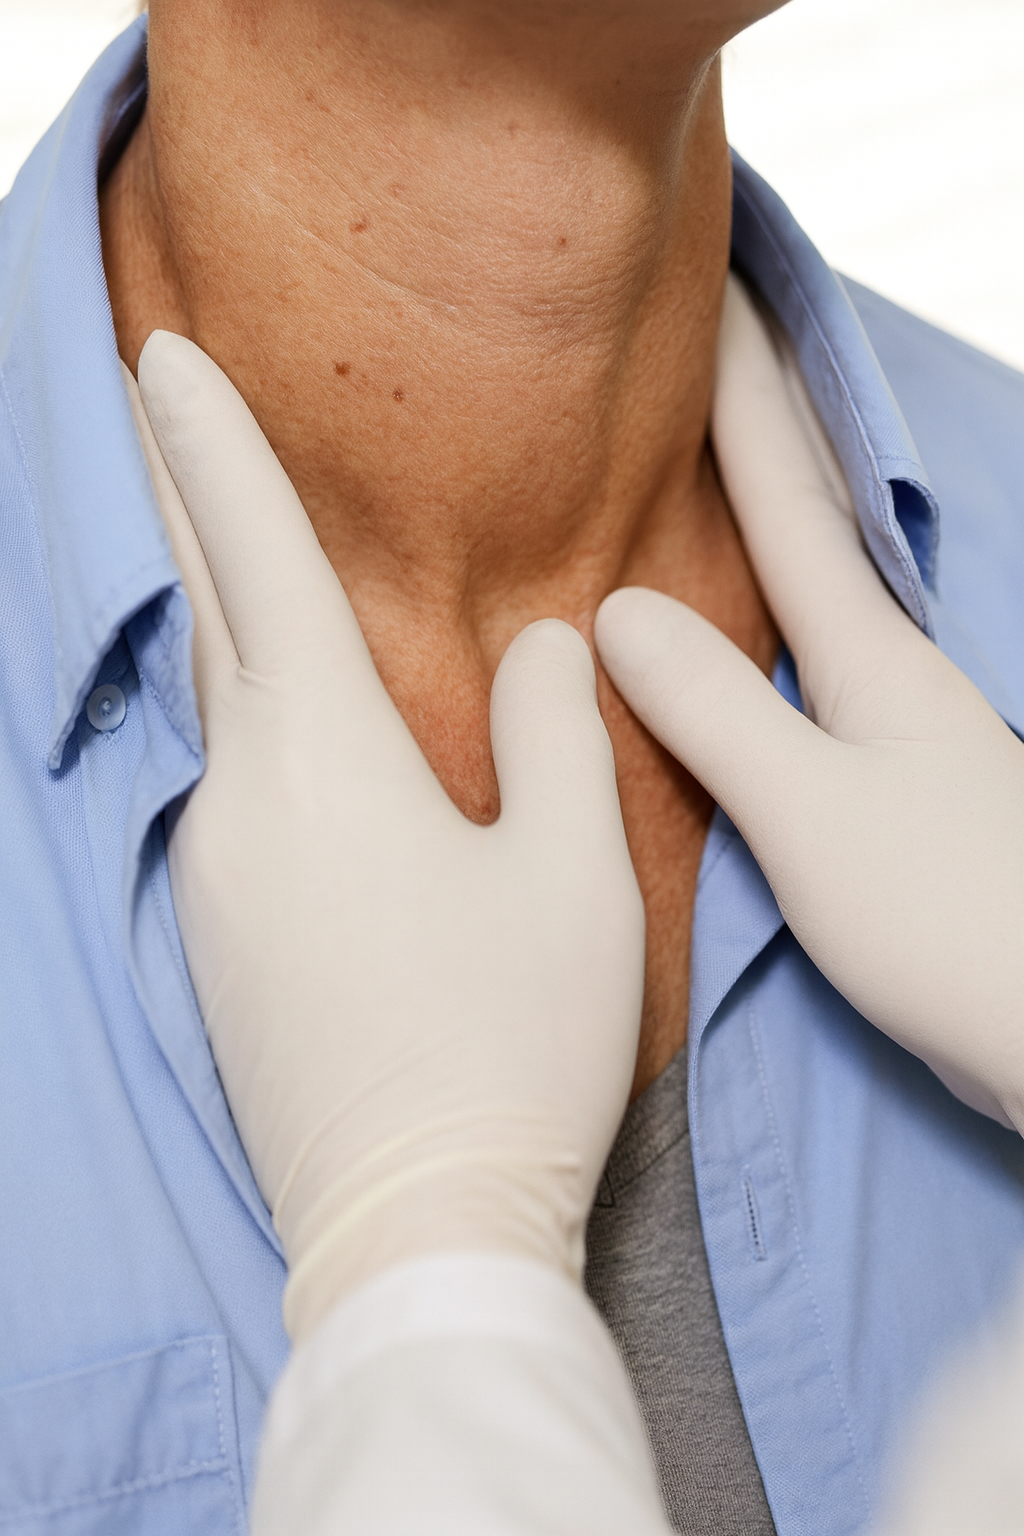

A tireoide ocupa um papel fulcral na coordenação do metabolismo e na harmonização do balanço energético do nosso organismo. Quando essa glândula não opera adequadamente,

O hipotireoidismo é uma condição médica que ocorre quando a glândula tireoide não produz hormônios em quantidades suficientes para o bom funcionamento do corpo. Esses

O hipotireoidismo é uma condição de saúde onde a glândula tireoide não produz hormônios em quantidade suficiente, o que pode afetar diversas funções do corpo